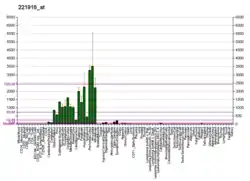

Neurofilament light polypeptide, also known as neurofilament light chain, abbreviated to NF-L or Nfl and with the HGNC name NEFL is a member of the intermediate filament protein family. This protein family consists of over 50 human proteins divided into 5 major classes, the Class I and II keratins, Class III vimentin, GFAP, desmin and the others, the Class IV neurofilaments and the Class V nuclear lamins. There are four major neurofilament subunits, NF-L, NF-M, NF-H and α-internexin. These form heteropolymers which assemble to produce 10nm neurofilaments which are only expressed in neurons where they are major structural proteins, particularly concentrated in large projection axons. Axons are particularly sensitive to mechanical and metabolic compromise and as a result axonal degeneration is a significant problem in many neurological disorders. The detection of neurofilament subunits in CSF and blood has therefore become widely used as a biomarker of ongoing axonal compromise. The NF-L protein is encoded by the NEFL gene.[5][6] Neurofilament light chain is a biomarker that can be measured with immunoassays in cerebrospinal fluid and plasma and reflects axonal damage in a wide variety of neurological disorders.[7][8] It is a useful marker for disease monitoring in amyotrophic lateral sclerosis,[9] multiple sclerosis,[10] Alzheimer's disease,[11][12] and more recently Huntington's disease.[13] It is also promising marker for follow-up of patients with brain tumors.[14] Higher levels of blood or CSF NF-L have been associated with increased mortality, as would be expected as release of this protein reflects ongoing axonal loss.[15] Recent work performed as a collaboration between EnCor Biotechnology Inc. and the University of Florida showed that the NF-L antibodies employed in the most widely used NF-L assays are specific for cleaved forms of NF-L generated by proteolysis induced by cell death.[16] Methods used in different studies for NfL measurement are sandwich enzyme-linked immunosorbent assay (ELISA), electrochemiluminescence, and high-sensitive single molecule array (SIMOA).[17]